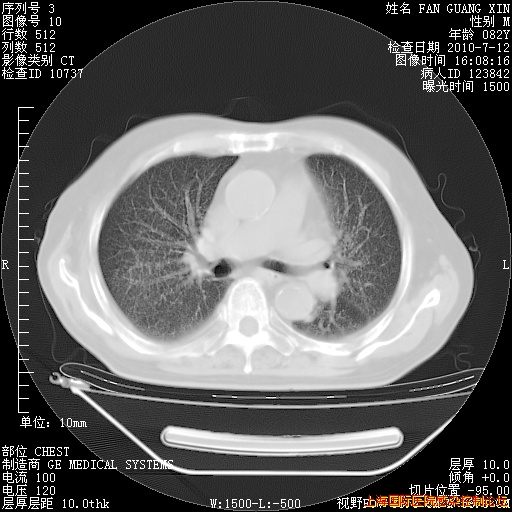

补发6月12日肺部CT肺窗

6月12日肺窗

今天复查CT

今天CT

整整相隔30天的肺部CT好像有所好转啊。甲强龙减量第3天,需要观察体温。